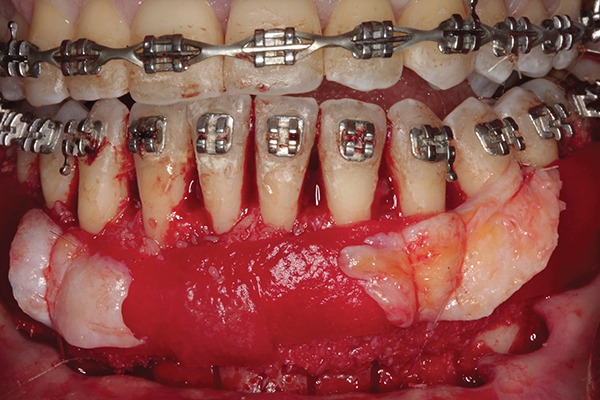

Fig 4. Particulate corticocancellous mineralized freeze-dried bone allograft in place on the left half of the mandible for periodontal regeneration and alveolar augmentation.

Figure 4

Fig 5. Bone grafting complete. Collagen wound dressing in place for graft stabilization and autogenous connective tissue grafts in

place, teeth Nos. 21 and 22 and Nos. 27 and 28, for simultaneous soft-tissue augmentation.

Figure 5

Fig 6. Tension-free wound closure.

Figure 6

Fig 7. Preoperative CBCT 3D tooth position and regional bone anatomy. Note maxillary hypoplasia, malocclusion, and dentoalveolar deficiencies.